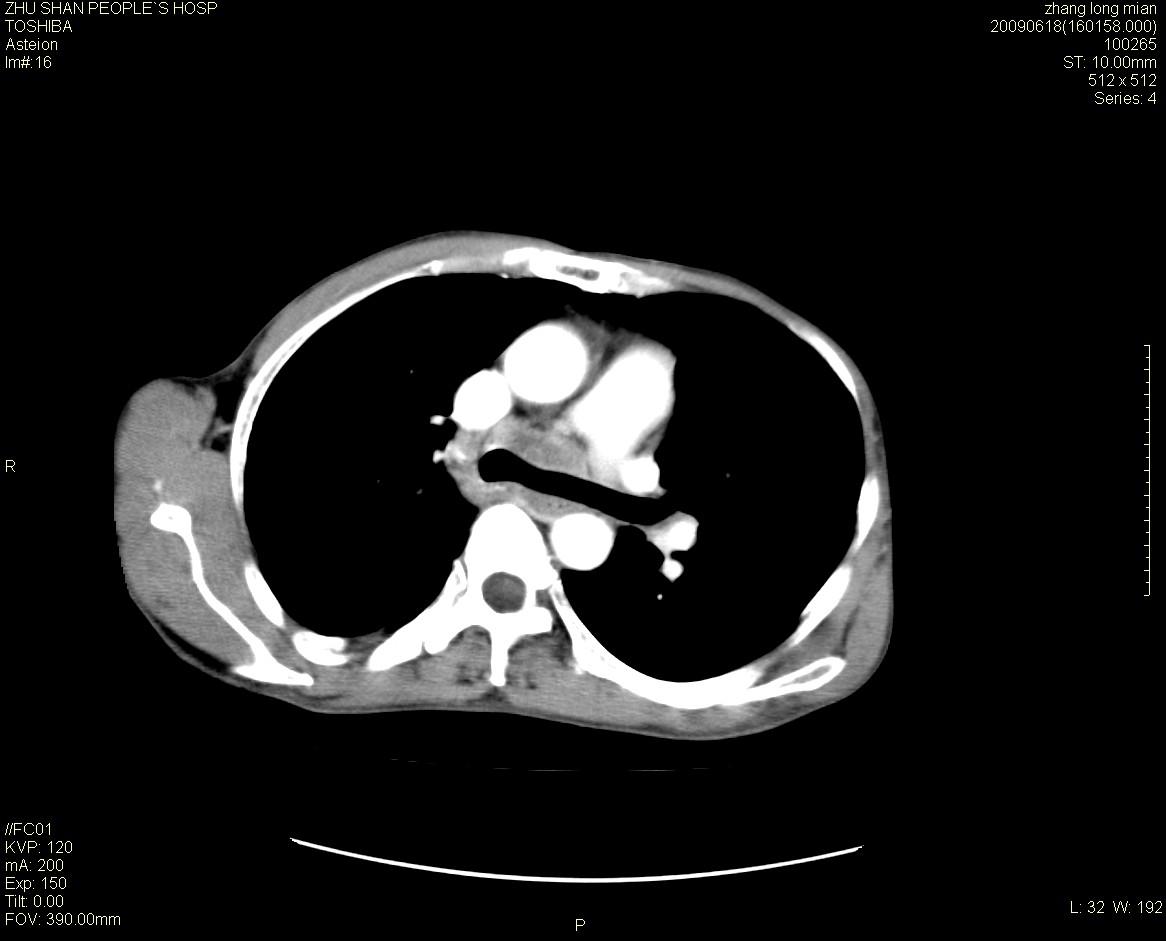

男性 65岁 胸片发现右下肺包块.诊断肺ca并纵隔转移没有问题吧!

两侧胸廓不对称,右侧呈塌陷改变,右肺萎缩。

右下肺见浅分叶状软组织块影,边缘有毛刺,其下部似见不完整偏心空洞影,邻近胸膜凹陷征,并胸腔积液。

增强见纵隔区气管隆突上下及左肺门区肿大淋巴结。左肺感染性病灶。

另见右上肺见一枚小结节影,性质待定。